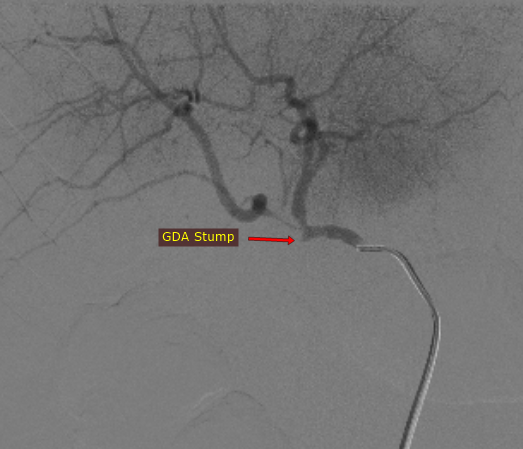

@iRadBIR_Chennai @SRajesh_IR @karananandpara @iRadRock @keithppereira @ChengaziMD @Murthy_CS_ @PulkitRangarh @drochohan I would still trap the aneurysm via SMA. Stenosis is distal to the GDA stump. So it should largely make no difference. It may be vasospasm which may get relieved.

A straightforward GDA Pseudoaneurysm embolization. But Angiogram looks like this, how would you proceed further? #iRad #MedTwitter @SRajesh_IR @karananandpara @iRadRock @keithppereira @ChengaziMD @Murthy_CS_ @lenonjdee @PulkitRangarh @drochohan @ChengaziMD